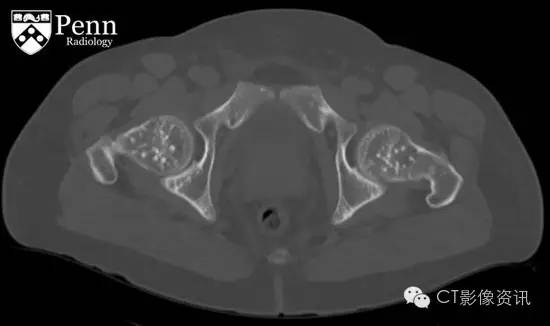

腹盆部冠状位以及轴位CT影像骨窗显示多个边界清晰的细小硬化灶呈现圆形、卵圆形以及线样;其直径从几毫米到一厘米不等,分布在股骨以及髋臼顶部;不伴有骨膜反应和骨质破坏。在软组织窗冠状位CT图像显示双侧肾影增大,伴随大量囊样密度影;此外在肝脏也可见囊样密度;可能为常染色体显性遗传多囊肾后遗症导致。

最终诊断:骨斑点症